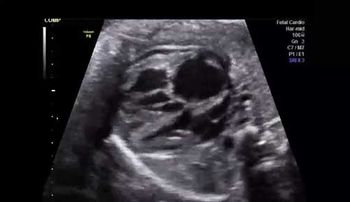

Challenge your diagnostic skills: See anything out of the ordinary in this second trimester fetal heart study?